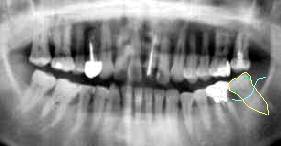

56歳・女性 │7抜去歯牙

│7一体どうなってるの? 抜歯してみて驚き, この core !

所見:│678周囲の歯肉が腫脹し動揺と排膿が認められた。 特に、│7は著明。

処置:│7が保存不可能なことを説明し、即日抜歯。│6のスクリューピン も髄床底に穿孔しており、また口蓋根の二次カリエスが著明であったため口蓋根ヘミセクション施行。 │DE7GBridgeの予定。

感想:“穿孔”にも程がある!よくこれでコアーの印象が採れたものだと (アマルガム?)関心する一方で、 術者の腕と感覚にあきれるばかり…おまけに│6の穿孔。思わず苦笑い。